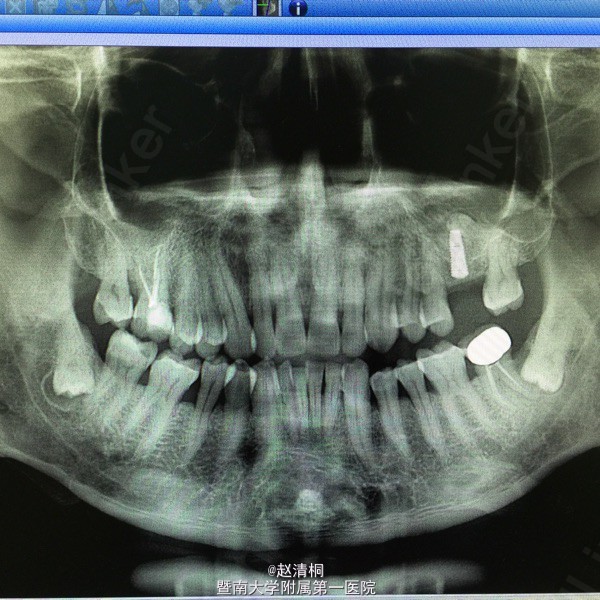

转透骨皮质后,即用上颌窦提升工具从小于植体直径慢慢敲入,提升后,植入10mm种植体。

3mm骨量,外提指征,上颌窦黏膜只要慢慢做,没那么容易破!